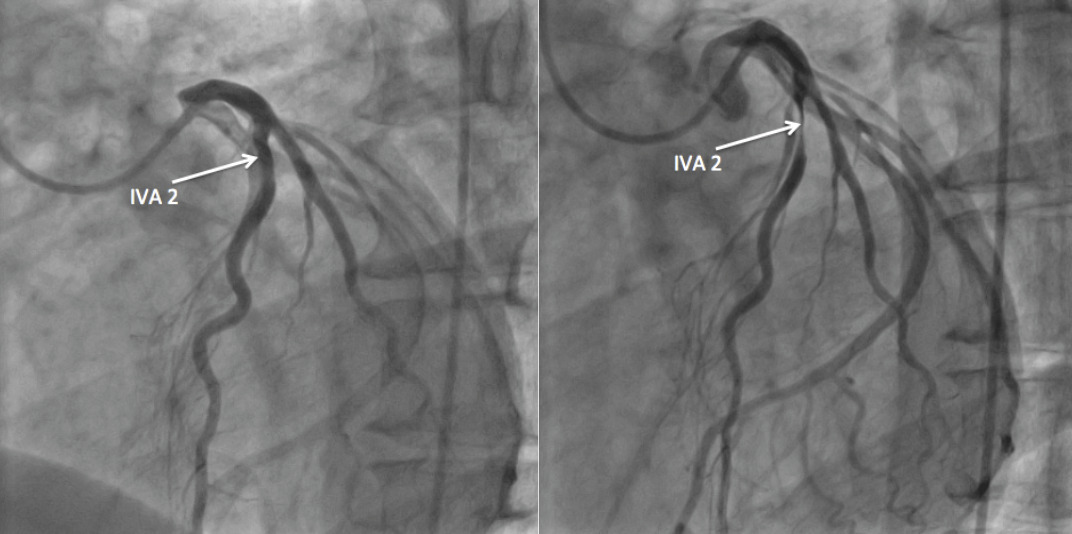

L’évolution de la plaque d’athérome rompue est parfois moins défavorable : le thrombus mural peut progressivement être englobé par le processus fibreux de cicatrisation. La lésion est alors plus sténosante, éventuellement symptomatique, mais moins sujette au risque de rupture et de complications ; sa structure est en effet dépourvue de centre lipidique et plus riche en fibres collagènes. Cette « stabilisation » de la plaque requiert plusieurs semaines (3 mois au maximum).Lorsque la symptomatologie est stable, il n’y a pas de risque d’évolution brutale vers l’occlusion et l’infarctus du myocarde. Cela ne préjuge cependant en rien de la sévérité des lésions et de leur diffusion. Aussi, lorsque la symptomatologie angineuse est ancienne, sans aggravation récente et laisse supposer des lésions stables, la coronarographie reste nécessaire, notamment chez les sujets de moins de 80 ans. Elle permet de détecter les lésions qui relèvent d’une revascularisation systématique en raison d’une évolution spontanée péjorative (sténoses du tronc commun et de l’artère interventriculaire antérieure [IVA] proximale ainsi que les atteintes tritronculaires à mauvaise fonction ventriculaire gauche).